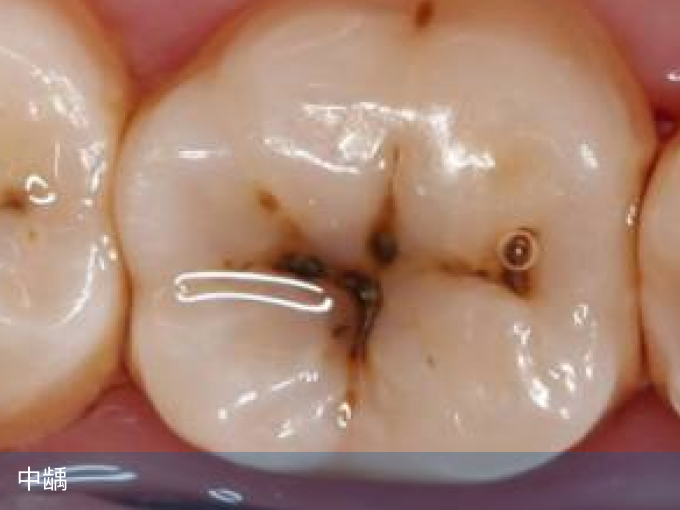

2、中龋

龋坏已经达到牙本质,出现明显的龋洞,进食时可出现轻微疼痛,提示属于中龋,需要及时补牙,价格为一颗牙200-500元。